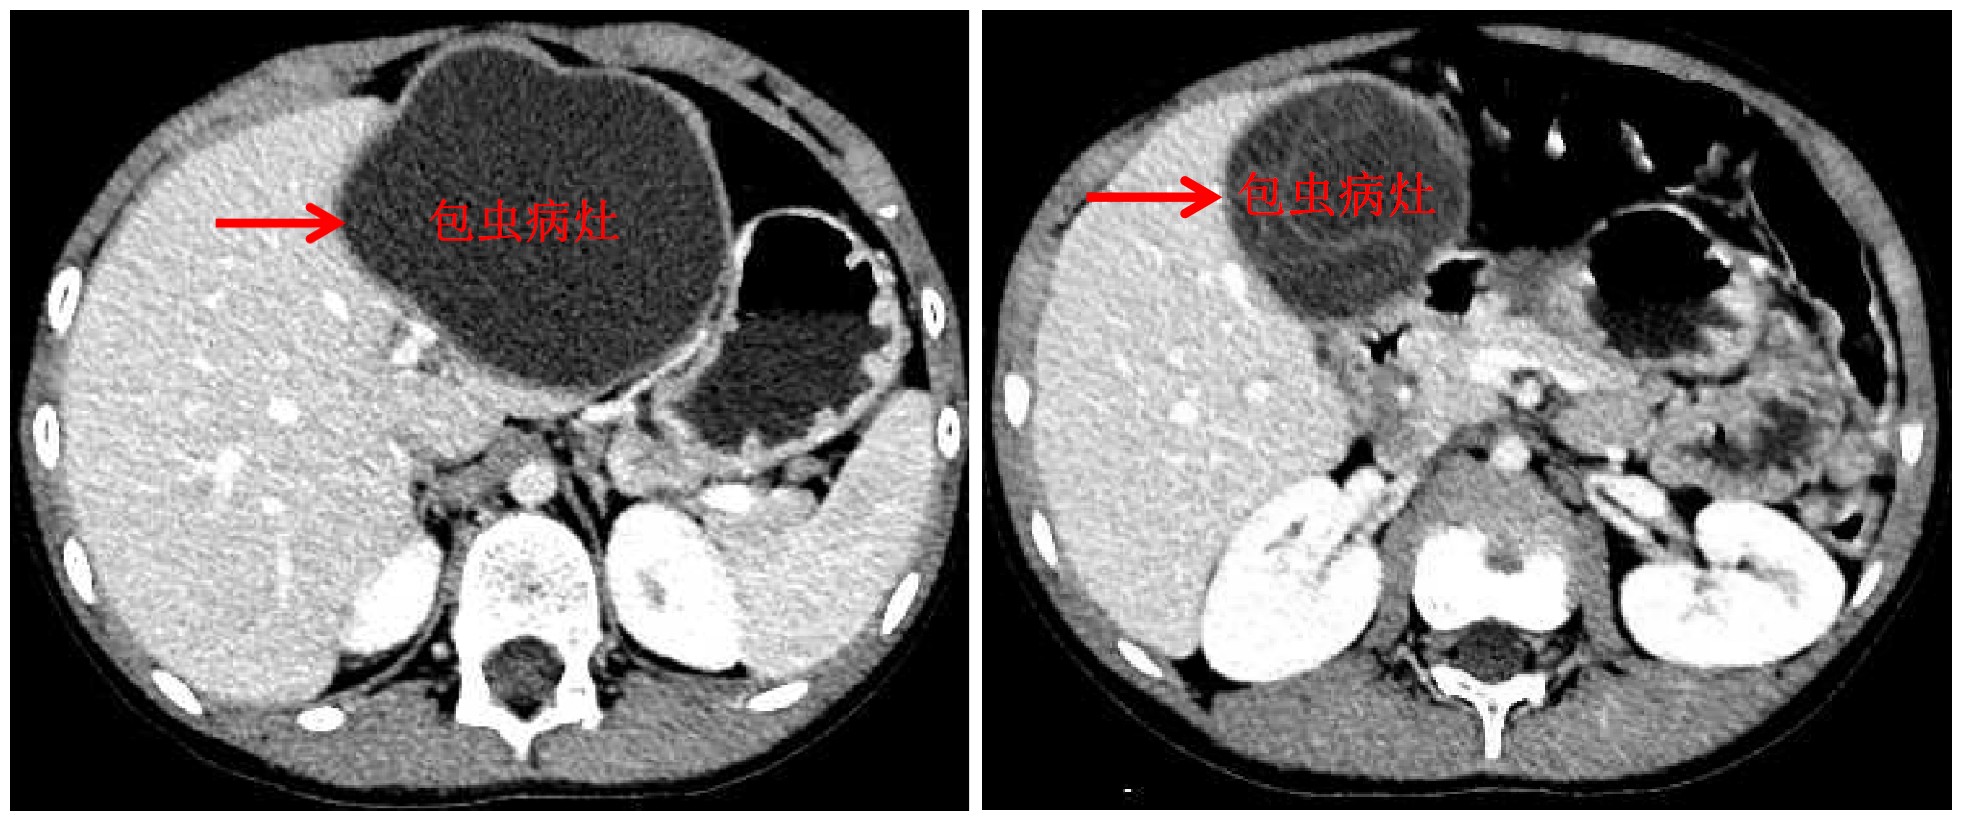

米兰新闻网10月13日电 国庆前,8岁的小扎西被父亲带到了西藏大学附属拉萨市人民医院普外科,此次距离孩子确诊肝包虫病已有一年之久。腹部影像显示,小扎西体内的囊型肝包虫病已经侵袭了左肝大部。

包虫病灶